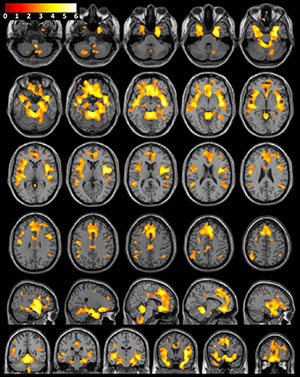

“We found that after an average of 13.5 months of abstinence, women who were previously dependent on stimulants had significantly less gray matter volume in several brain areas compared to healthy women,” said the study’s senior author, Jody Tanabe, M.D., professor of radiology, vice chair of Research, and Neuroradiology Section Chief at the University of Colorado Denver School of Medicine. “These brain areas are important for decision making, emotion, reward processing and habit formation.”

The researchers analyzed structural brain MRI exams in 127 men and women, including 59 people (28 women and 31 men) who were previously dependent on cocaine, amphetamines, and/or methamphetamine for an average of 15.7 years, and 68 healthy people (28 women and 40 men) who were similar in age and gender. The MRI results showed that after an average of 13.5 months of abstinence, women who were previously dependent on stimulants had significantly less gray matter volume in frontal, limbic and temporal regions of the brain.

“While the women previously dependent on stimulants demonstrated widespread brain differences when compared to their healthy control counterparts, the men demonstrated no significant brain differences,” Dr. Tanabe said.